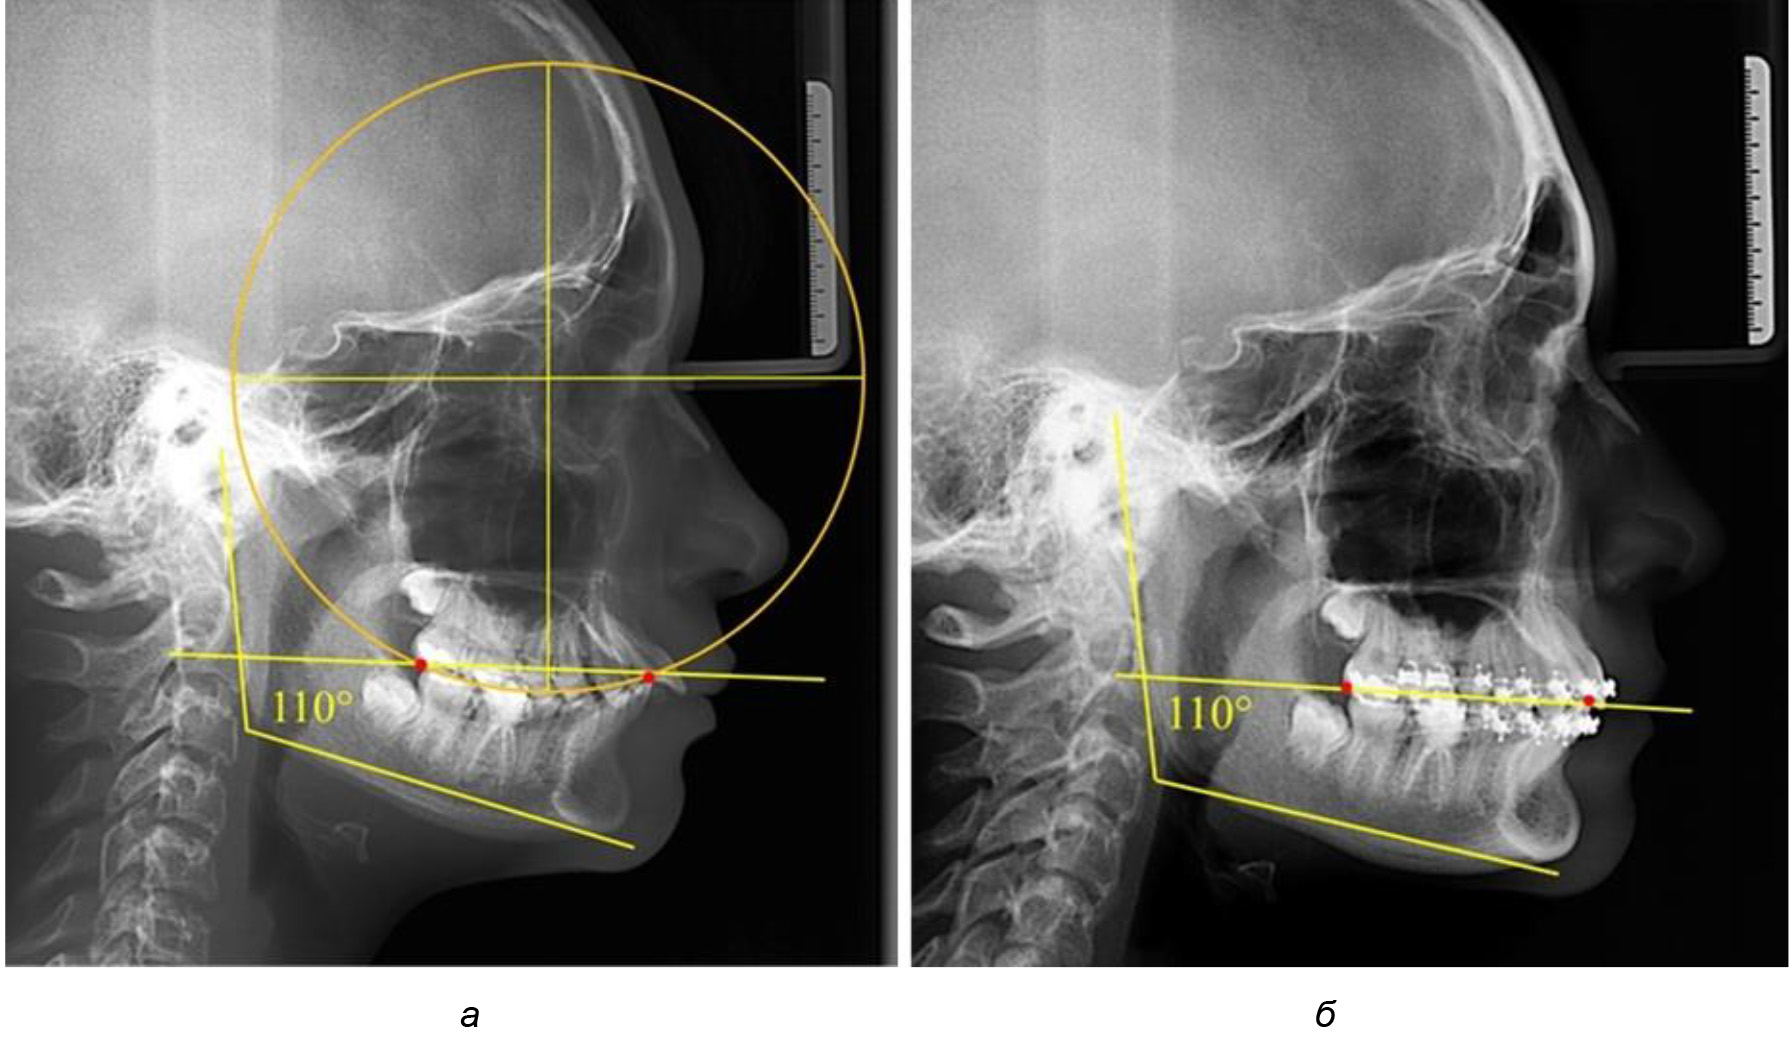

У людей с аномалиями окклюзии по сагиттали в 1-й подгруппе обследовано 9 человек. Обращает на себя внимание увеличение глубины кривой Spee, что нами расценивалось, как патологическая форма кривой линии окклюзии.

Глубина кривой Spee в среднем по 2-й подгруппе составила (5,69 ± 1,57) мм, что было достоверно больше, чем у людей с физиологической окклюзией (р ˂ 0,05). Достоверных различий с показателями, полученными при анализе ТРГ и ОПТГ, нами не отмечено (р ˃ 0,05). Отношение радиуса окружности к сагиттальному размеру окклюзионной линии в среднем по подгруппе составляло 1,372 ± 0,042 и не соответствовало числу Фибоначчи, что может быть использовано в качестве диагностического критерия определения патологической формы кривой Spee. После лечения пациентов техникой «прямой» дуги было отмечено незначительное увеличение сагиттального размера окклюзионной лини в среднем на (2,12 ± 0,77) мм. Однако окклюзионная линия практически касалась окклюзионного контура всех жевательных зубов, и отмечалось практически полное отсутствие кривой Spee.

Таким образом, проведенное лечение техникой «прямой» дуги способствует нормализации окклюзионного равновесия и торку передних зубов, однако не соответствует оптимальному окклюзионному статусу, характеризующему физиологическую окклюзию. При этом величина нижнечелюстного угла оставалась на прежнем уровне (рис. 5).

Рис. 5. Особенности ТРГ при патологической кривой Spee до лечения (а) и после лечения (б) техникой «прямой» дуги